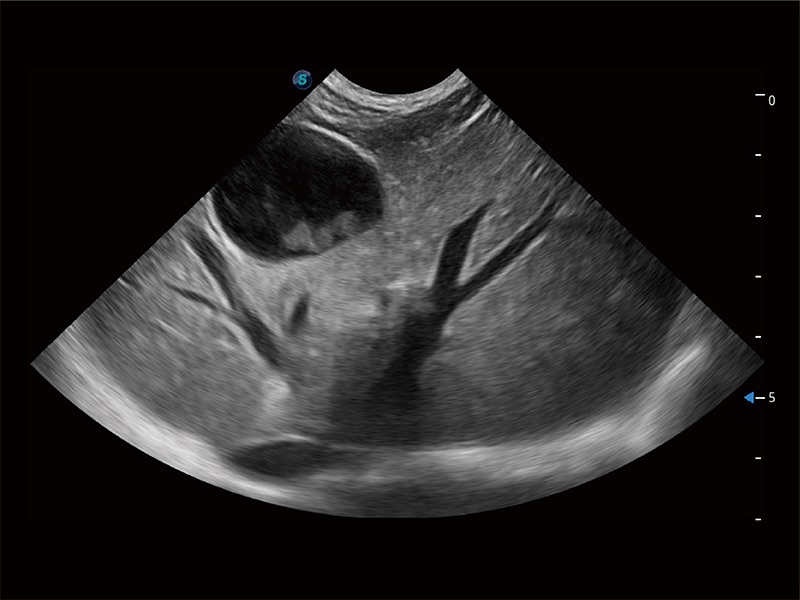

动物是人类最亲密的朋友和最值得信赖的伙伴。美狮贵宾会官网也一直致力于探索动物专用的超声影像解决方案。全新推出的ProPet系列,是美狮贵宾会官网在动物超声影像智能化、专业化、精准化的一次跨越式革新。动物不能用言语来表述自己的不适,通过超声影像,ProPet系列搭建了动物医生与不同物种沟通的“桥梁”,为动物医生注入了“治愈之力”。 ProPet 80 是美狮贵宾会官网匠心打造的一款高端动物专用彩超,采用性能卓越的全新硬件架构,极大提升超声系统的运行效率和数据处理能力,帮助动物医生从容应对日益增多的挑战性病例和日益多样化的临床需求。

高性能和先进的临床应用工具可以为动物医生提供临床信心。ProPet 80 搭载了先进的腹部和浅表应用工具,帮助医生在日常临床实践中发挥前所未有的作用。

ProPet 80 全新的动物超声智能软件和丰富的探头群,为动物医生提供了高清晰度和精细分辨率的图像,无论在宠物、马科、畜牧还是实验室动物等应用中都可以轻松应对,为您的日常工作带来满意的体验。